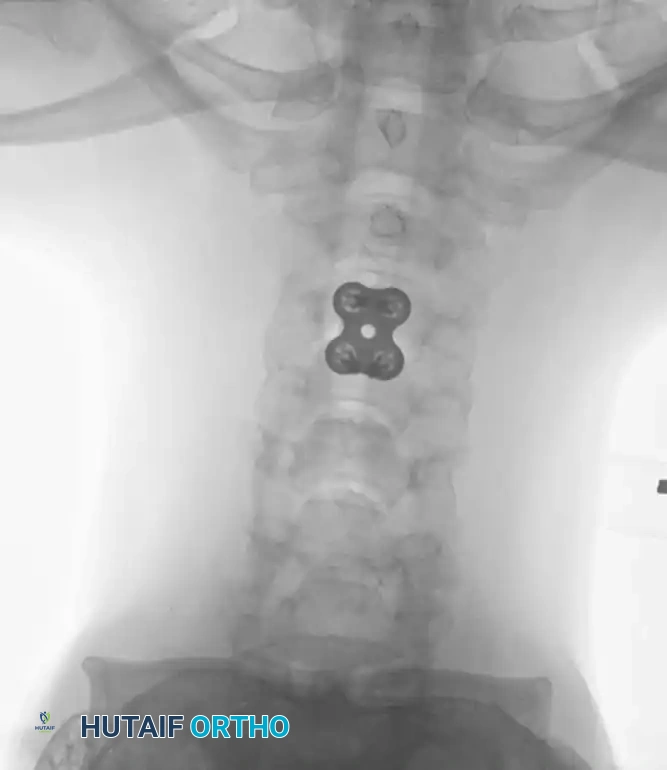

Anterior Plating Technique (Technique 35-16)

When anterior column reconstruction is required (e.g., post-corpectomy), anterior plating provides rigid stabilization.

- Measurement and Selection: Measure the distance between the middle of the cranial vertebra and the middle of the caudal vertebra to be included in the fixation. Use this caliper measurement to select the appropriate plate length.

- Contouring: If necessary, use a plate bender to conform the plate to the patient's specific spinal anatomy. Make several slight bends along the length of the plate and between the screw holes to obtain a consistent radius of curvature.

- Positioning: Using a plate holder, place the plate on the vertebral column in the optimal anatomical position.

- Temporary Fixation: Temporarily fix the plate with small pins screwed into the cortical wall. Insert these self-cutting pins diagonally through the screw holes to obtain sufficient provisional stability.

- Drilling: Place the drill guide on the plate. The guide limits pilot holes to the orientation of the integrated blocking ring (0 to ± 10 degrees sagittally and 6 degrees axially). Use the appropriate drill bit (10 mm, 12 mm, 14 mm, 16 mm, or 18 mm) to prepare the pilot hole.

- Screw Insertion: While tapping is an option, modern screws are typically self-tapping. Insert the 4.0-mm or 4.5-mm screws into the pilot holes. Tighten until locked into the plate, ensuring the locking mechanism (washer) fully covers the screw head.

- Graft Securing: If a corpectomy and structural grafting were performed, secure the graft to the plate using standard 4-mm screws placed in the intermediary screw holes.

- Closure: Thoroughly irrigate the wound and close in layers over a subfascial drain.

Associated Surgical & Radiographic Imaging